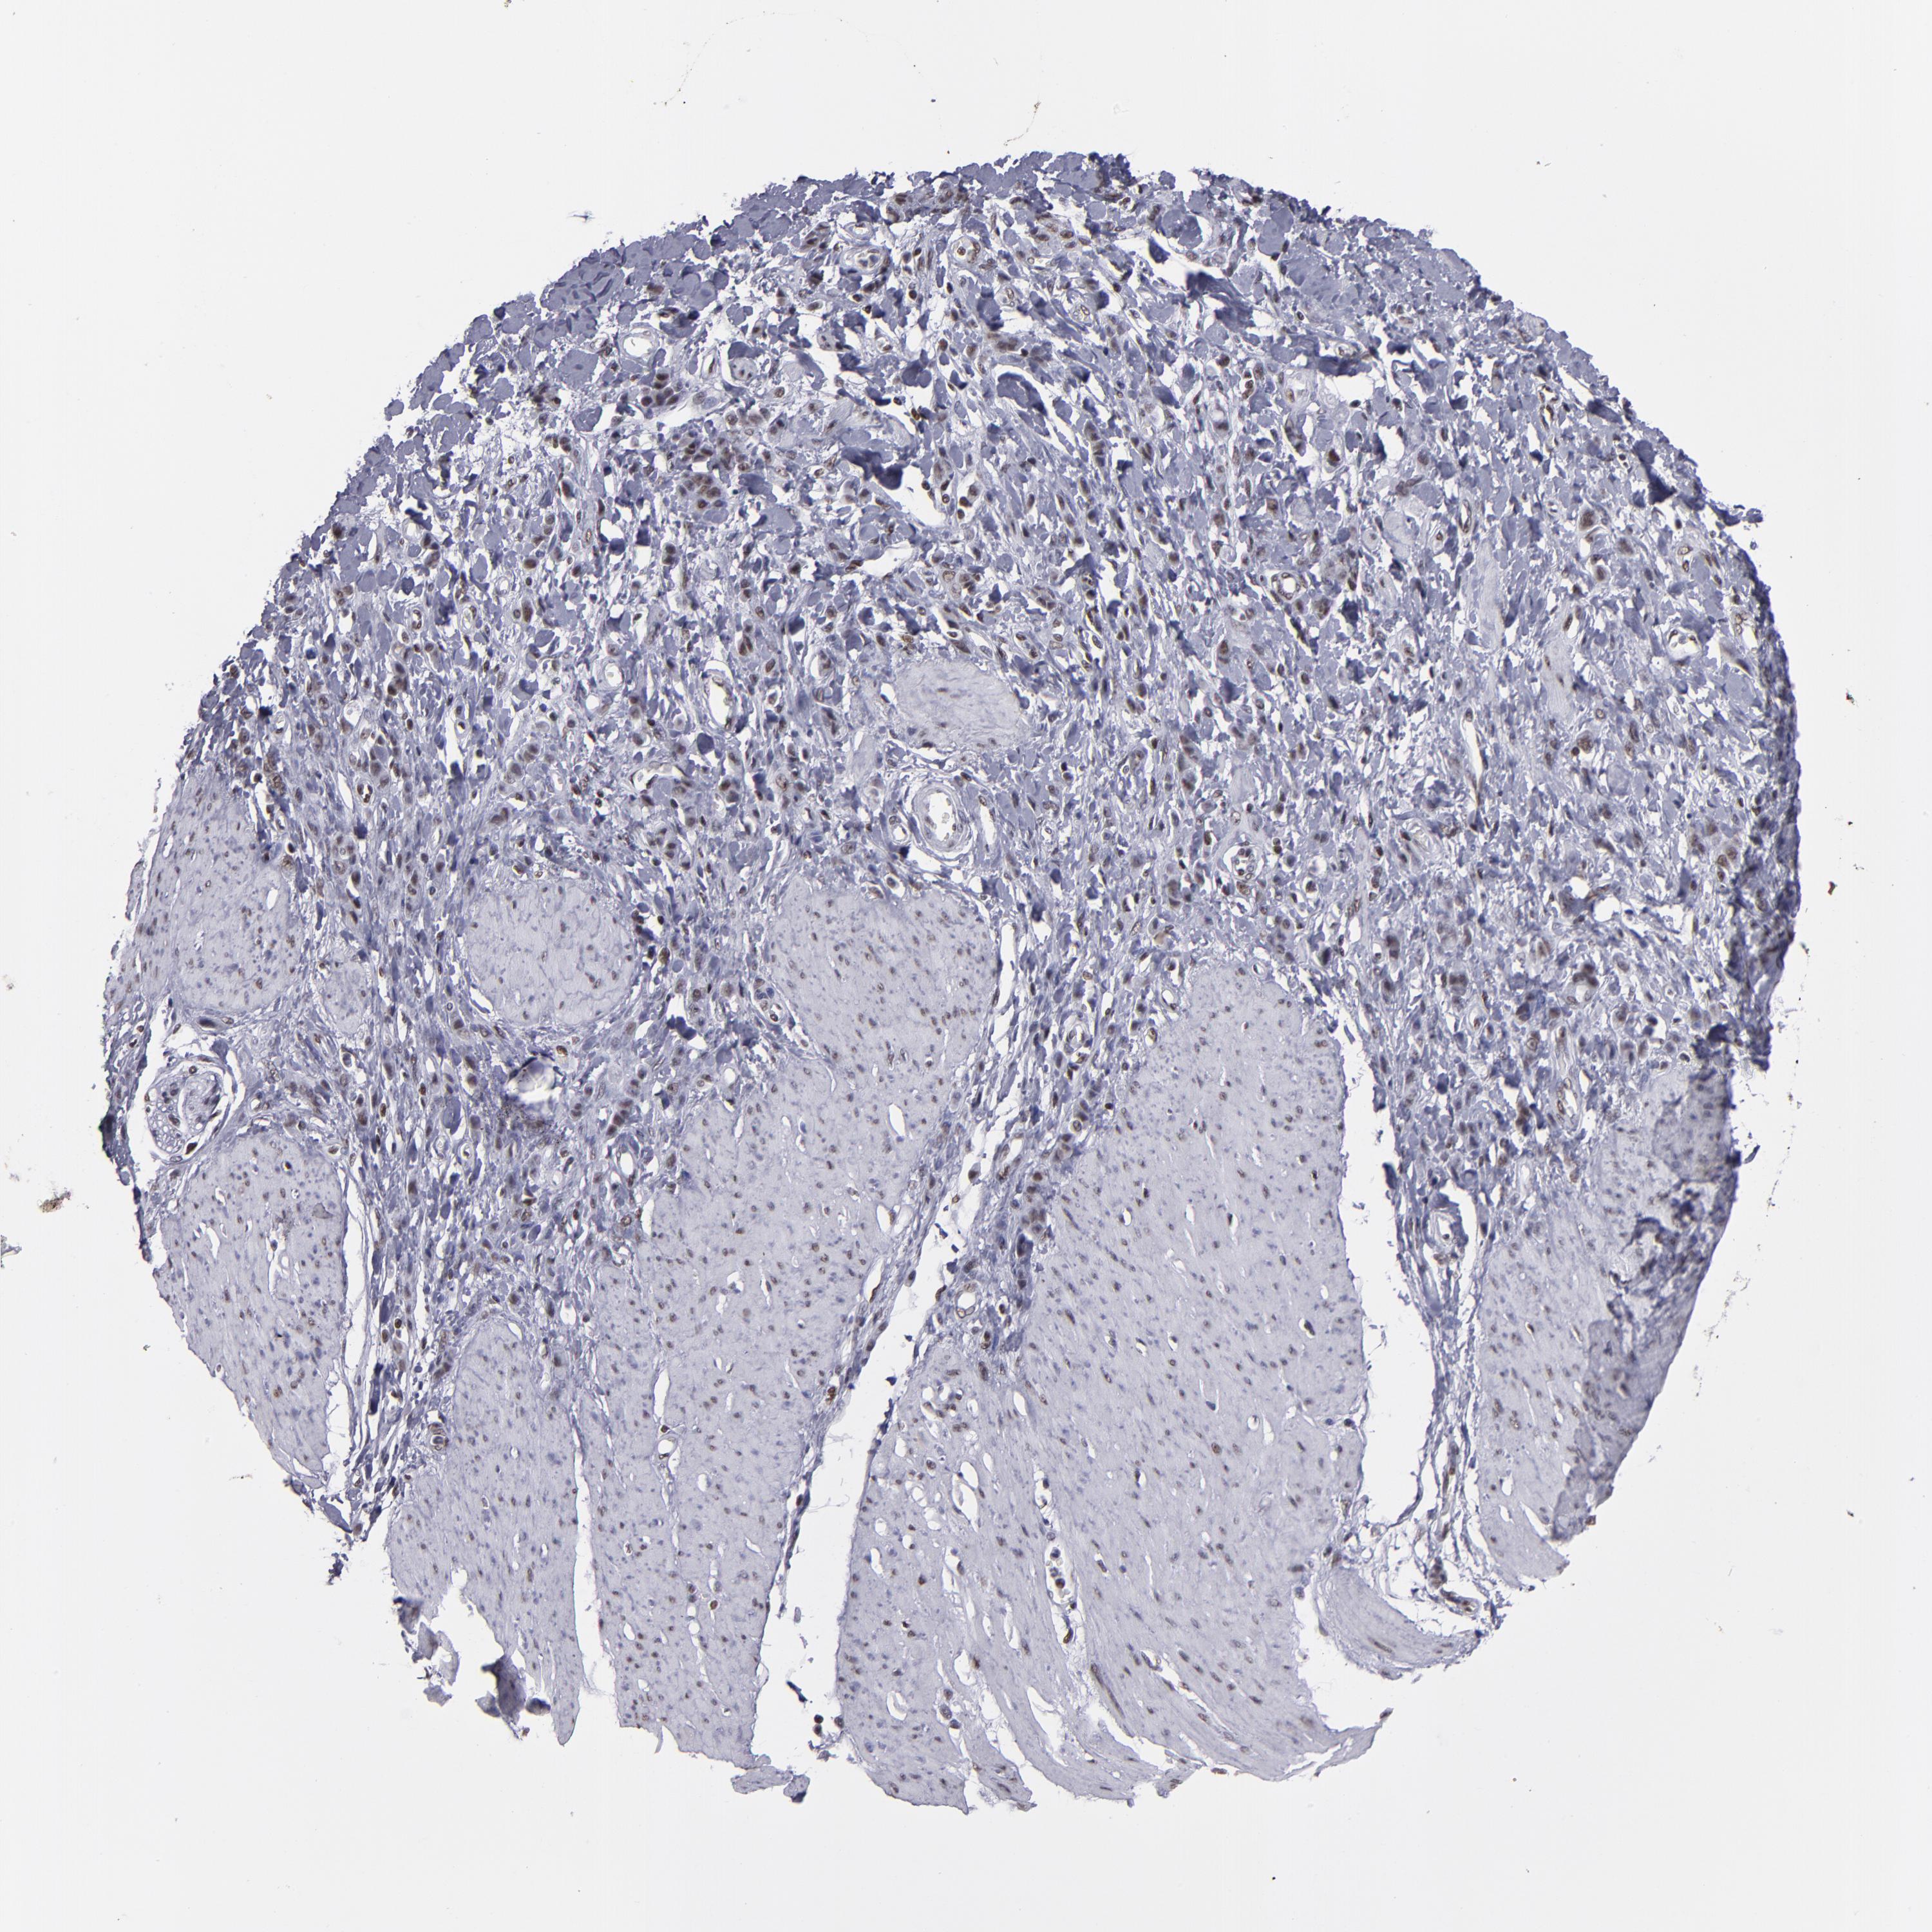

STOMACH CANCER - Protein expressioni

A mouse-over function shows sample information and annotation data. Click on an image to view it in a full screen mode. Samples can be filtered based on level of antibody staining by selecting one or several of the following categories: high, medium, low and not detected. The assay and annotation is described here.

Note that samples used for immunohistochemistry by the Human Protein Atlas do not correspond to samples in the TCGA dataset.

Antibody stainingi

Antibody staining in the annotated cell types in the current human tissue is reported as not detected, low, medium, or high, based on conventional immunohistochemistry profiling in selected tissues. This score is based on the combination of the staining intensity and fraction of stained cells.

Each image is clickable and will lead to virtual microscopy that enables deeper exploration of all samples and also displays staining intensity scores, fraction scores and subcellular localization as well as patient and tissue information for each sample.

Antibody HPA001907

Antibody HPA002735

Antibody CAB010451

Antibody CAB080271

Staining

High

Medium

Low

Not detected

Intensity

Strong

Moderate

Weak

Negative

Quantity

>75%

75%-25%

<25%

None

Location

Nuclear

Cytoplasmic/membranous

Cytoplasmic/membranous,nuclear

Adenocarcinoma, NOS

Adenocarcinoma, High grade